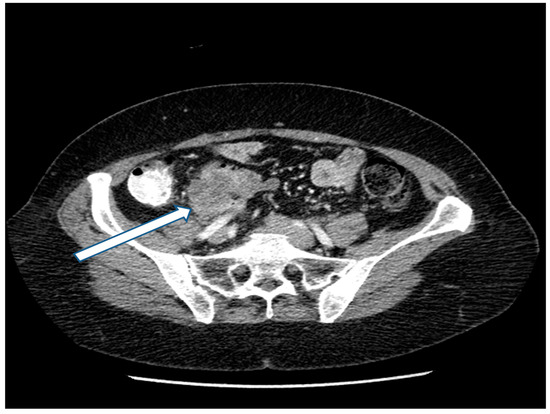

27 May 2018: Patient was asymptomatic. CEA increased from 3.0 to 20 ng/mL. CT showed a mass in the left paracolic gutter. Biopsy of this mass showed adenocarcinoma. A 1.5 cm mass was present at the ileocolic anastomotic site (Figure 2). A second mass was demonstrated in the rectovesical space (Figure 3). FOLFIRI was initiated. CEA increased to 74 ng/mL.

Figure 2. CT demonstration at the time of recurrence of a mass in the left paracolic sulcus. CT-guided biopsy showed adenocarcinoma.